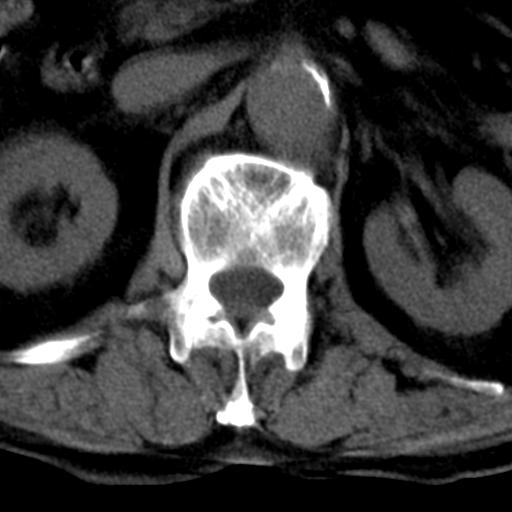

男性 82 主动脉夹层 请大家看看椎体是什么改变啊

腰椎退行性变,明显的骨赘形成,所指低密度灶为正常松质骨。